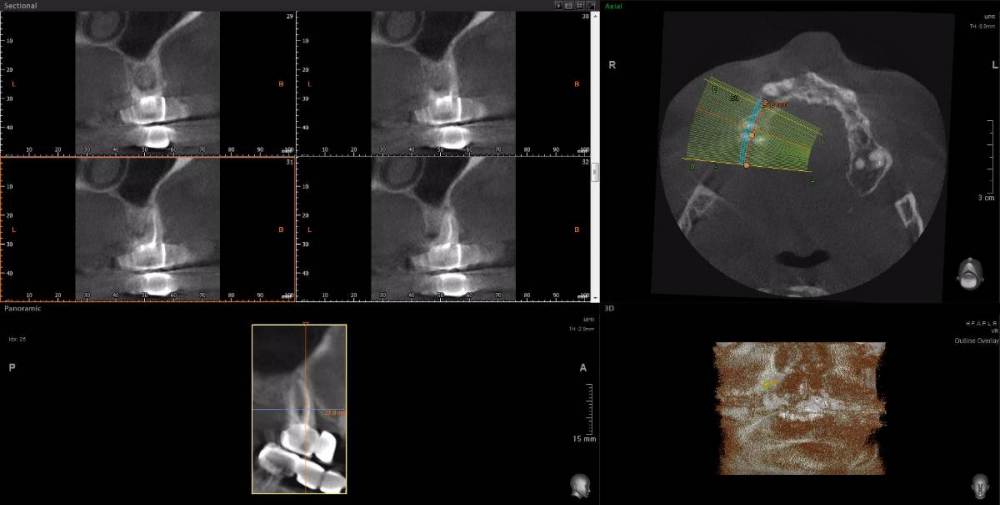

Dude Опубликовано 1 апреля, 2021 Поделиться Опубликовано 1 апреля, 2021 По плану в 1 этапе, кроме остального: лечение каналов и укрепление их стекловолоконными штифтами: 16, 25, 27, 44, 47; имплантация 14, 15, 17, 12, 11, 21, 22, 24, 26, 36, 37, 46, 45. Во 2 этапе (через 5-6 месяцев) установка коронок. Лечение в другой стране. Чтобы сократить длительность первого этапа, предложили лечение зубов сделать на 2 этапе. Очень засомневался, можно делать имплантацию с невылеченными зубами? Ссылка на комментарий

Dude Опубликовано 1 апреля, 2021 Автор Поделиться Опубликовано 1 апреля, 2021 https://disk.yandex.ru/d/6d0pmZ1zArn1Og Так? Ссылка на комментарий